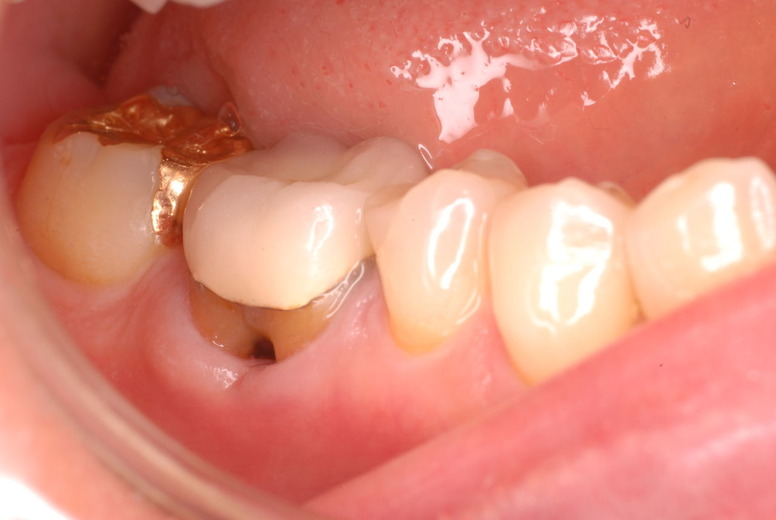

親知らずを取ることを嫌がる方が多いのですが、もし親知らずとその隣の14歳大臼歯の間に虫歯ができたり歯周病を罹患した場合、どれほど治療が大変で再発も起こりやすいか理解できない方がおおいのです。

写真左下の親知らずが痛くなり抜歯しました。その後歯茎を除去して虫歯を露出させる処置を二回ほどしています。

レントゲンでは小さいですが、こう言う虫歯が一番怖いのです。

治療の成功率は極めて悪くすぐ再発しやすいのです。